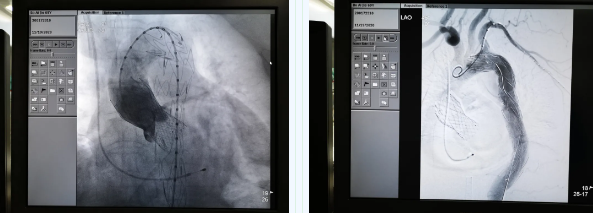

張金洲副院長關(guān)注著手術(shù)的每一個細節(jié),從建立軌道、跨瓣、釋放瓣膜、支架定位、造影和食道超聲確認,每一步都緊張而有序地進行著。為了最大程度保障病人安全,心臟外科程亮副主任也帶隊建立動靜脈入路,以備緊急體外循環(huán)。經(jīng)過團隊每一位成員的密切配合,在近四小時的緊張奮戰(zhàn)之后,“TAVR TEVAR”復(fù)合手術(shù)順利完成;經(jīng)過造影和食道超聲證實:人工主動脈瓣無返流無瓣周漏、冠脈顯影良好,主動脈覆膜支架無內(nèi)漏無移位。